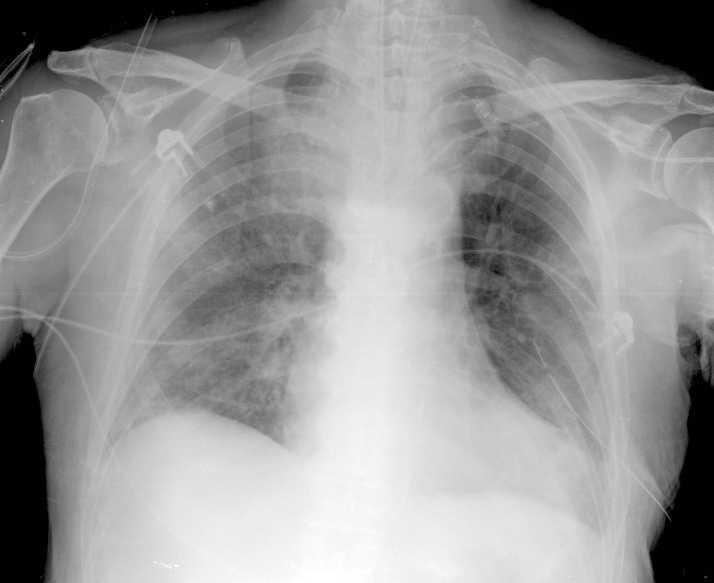

Acudió al Servicio de Urgencias por malestar general, anorexia y disnea progresiva de dos días de evolución. En la exploración destacaba saturación de O2 del 86% e hipoventilación de los dos tercios inferiores del pulmón izquierdo y tercio inferior del pulmón derecho. En la analítica presentaba 8.950 leucocitos/µl con 7,6% de eosinófilos, creatinina 3,1 mg/dl, sodio 126 mEq/l y gasometría venosa con pH 7,36, pCO2 26, PO2 31 y HCO3 15. Se realizó radiografía de tórax, en la que se observaba derrame pleural izquierdo masivo e infiltrado intersticial en pulmón derecho (fig. 1). Ingresó en el Servicio de Oncología procediéndose a toracocentesis evacuadora, de la que se obtuvieron 500 cc de líquido seroso compatible con trasudado. Dado el progresivo empeoramiento respiratorio se comentó el caso con nuestro Servicio, colocándose tubo endotorácico, sin mejoría clínica. Ingresó en la UCI, procediéndose a intubación orotraqueal y conexión a ventilación mecánica. Ante la posibilidad de toxicidad pulmonar por interleucina se suspendió el tratamiento inmunomodulador y se inició tratamiento corticoideo, con resolución completa del cuadro clínico y radiológico (fig. 2), pudiendo ser extubado en 48 horas sin complicaciones. El examen citológico y microbiológico del lavado broncoalveolar y del derrame pleural fueron negativos para malignidad y estériles, mostrando infiltrado inflamatorio de tipo mixto.

Figura 1. Radiografía de tórax. Se aprecia derrame pleural izquierdo masivo e infiltrado intersticial en pulmón derecho.